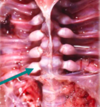

what disease is this?

rickets, this is showing the costochondral junction and the growth plates of ribs are being thickened and cartilaginous, looking like rosary beads